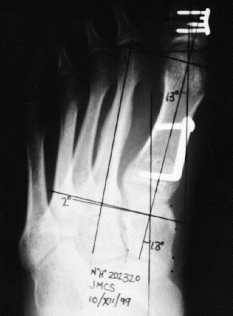

Los ángulos biomecánicos estudiados pasaron de un ángulo de hallux medio de 36° (preop.) a 10° (postop.) (3-15°). El ángulo intermetatarsiano medio pasó de 16° (preop.) a 5° (postop.) (2-9°). El ángulo cuneometatarsal medio pasó de 18° (preop.) a 11° (postop.) (5-16°). El ángulo interfalángico medio pasó de 6° (preop.) a 8° (postop.) (3-13°) (Fig. 2).

Fig. 2.--Radiografía anteroposterior de control tras la cirugía. Fig. 2.--Anteroposterior post-operative check X-ray.